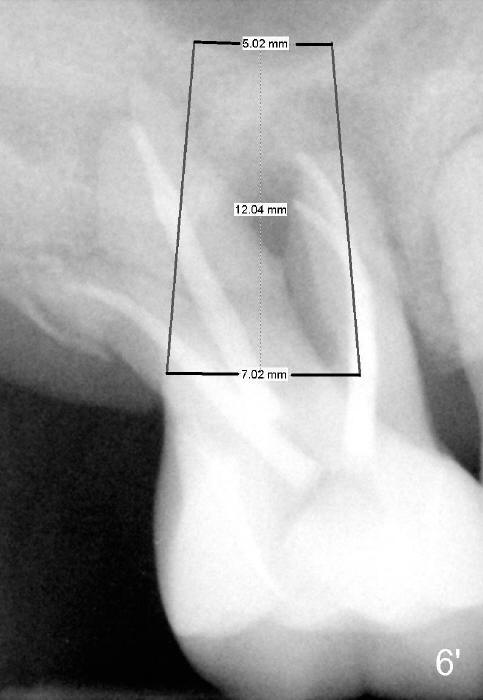

If the septum is basically intact, a 5.3x12 bone-level implant is placed in an ideal trajectory for restoration (Fig.3).  The mesial and distal margin of the implant is at the level of the alveolar crests (arrows); bone graft is placed evenly to cover the coronal threads (red circles). If the septum is defective to some degree, a longer implant is placed distally (Fig.4) with more bone graft placed distally.  Or the implant is placed deeper (Fig.5).  If the septum is severely defective, an extra wide, but shorter implant (6.9x10 mm bone-level SM) is used (Fig.6).  Or an extra wide UF implant with extra 2 mm length may offer better primary stability (Fig.6' (with sinus lift)).  The primary stability of the extra wide implants is derived from contact with the mesial and distal socket walls.